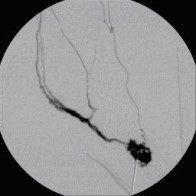

Perkutane Embolisation einer low-flow venösen Malformation (Gefäßmissbildung) der Fußsohle-1

(Bild 4 von 5)

Perkutane Embolisation einer low-flow venösen Malformation (Gefäßmissbildung) der Fußsohle-2

(Bild 5 von 5)